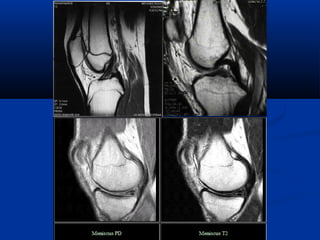

Diffusion Perfusion

Diffusion Tensor MRI

(DTMRI)